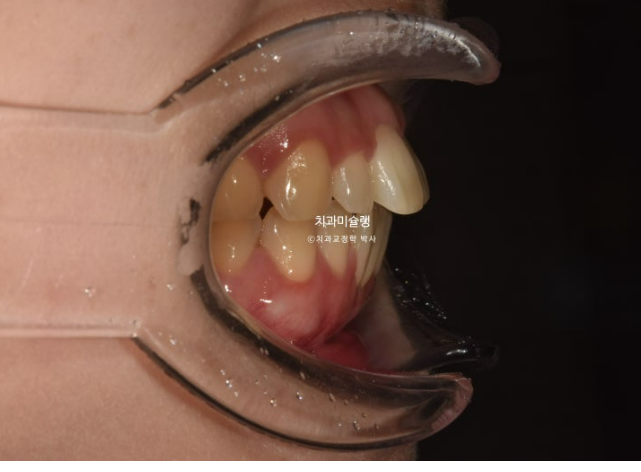

안모에서는 입술에 힘을 빼면 살짝 벌어지는 입술부전증이 보입니다.

24.06

원인은 위 앞니 돌출 때문입니다.

치료계획은 비발치로 사랑니 공간으로 어금니들을 뒤로 밀어 돌출을 해소하고 개방교합, 가위교합 등을 개선하기로 합니다.